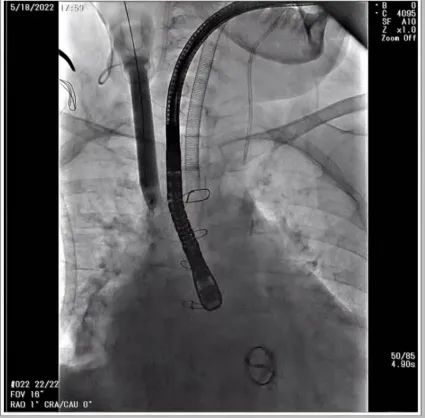

根据术前评估结果,郭应强教授团队为患者量身定制了手术策略,决定使用LuX-Valve Plus经血管三尖瓣置换系统开展手术治疗。手术在全麻下进行,采用经右侧颈静脉入路,在经食道超声和DSA的指引下调整输送器角度以达到正确位置,勾住前瓣后逐步释放盘片,盘片打开后顺利扎针,最终完成瓣膜植入,输送器撤出。术后超声提示人工三尖瓣同轴性良好,瓣架固定牢靠,无反流和瓣周漏,术后三尖瓣平均跨瓣压差为1 mmHg。

术前DSA造影